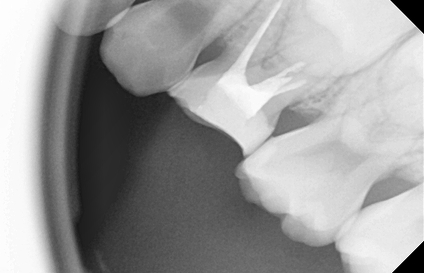

유치는 영구치보다 충치의 발생빈도 및 진행속도가 빠릅니다.

특히 치아 사이면이 쉽게 썩는데, 잘 보이지 않아 가정에서 충치를 발견했을 때에는 이미 치료시기를 놓친 경우가 많습니다.

한편, 유치 치수(치아신경)는 상대적으로 커 조금만 깊이 충치가 진행되면 신경치료까지 해야 하는 경우가 많습니다.

유치를 제 때 치료하지 않으면 뿌리 쪽에 고름이 생겨 유치 아래에 숨겨져 있는 영구치에 손상을 줄 수 있으며,